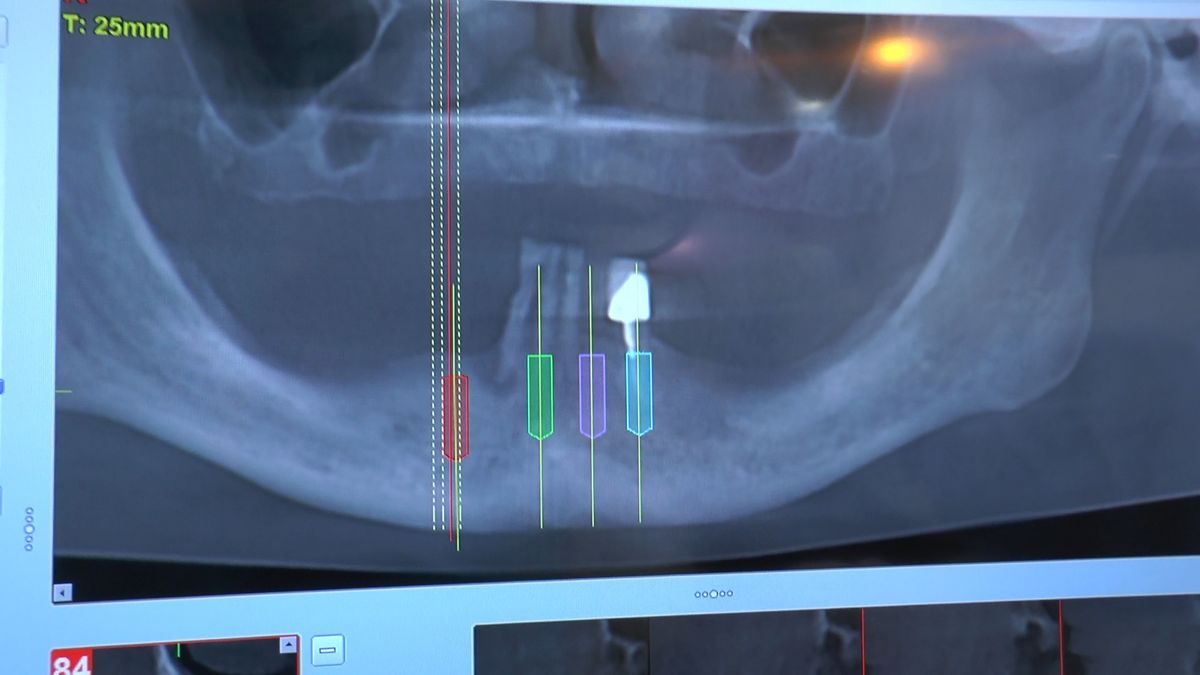

Pierwszy weekend 2019 roku w Instytucie Vivadental, to doskonałe otwarcie kolejnego roku edukacyjnego i szkolenia naszych Kursantów. W drodze do sukcesu w implantologii zdobywają wiedzę i umiejętności, a każdy kolejny zabieg to impuls i inspiracja do twórczego rozwoju w leczeniu własnych Pacjentów. Rozpoczęliśmy od sesji praktycznej implantologicznej właśnie z udziałem Pacjentów, na której dominowały samodzielne zabiegi wykonywane pod kierunkiem Mentorów – dr n.med. Violetty Szycik i dr n.med. Magdaleny Kisłowskiej – Syryczyńskiej. W ciągu dwóch dni zabiegowych przyjęliśmy 14 Pacjentów, przeprowadziliśmy zabiegi chirurgiczne, zabiegi regeneracyjne tkanki kostnej i augmentacji oraz wszczepiliśmy 20 implantów systemu Axiom. W ramach panelu edukacyjnego Sukces Twojego Biznesu odbyły się kolejne zajęcia z NLP, na których nasz Mentor Mariusz Wójcik z Gdańskiej Akademii Umiejętności Menedżerskich, kontynuował wprowadzenie do psychologii i podstaw kierujących decyzjami Pacjentów. Ćwiczenia w wesołej i koleżeńskiej atmosferze były niezwykle pouczające, a jednocześnie stanowiły idealną odskocznię po wyczerpujących zabiegach.